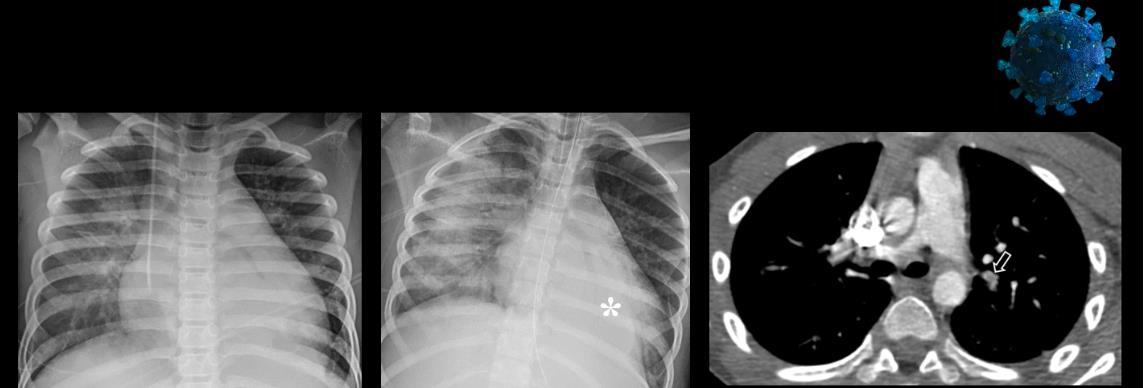

Imaging of Covid 19 infection in children CXR 9 C O V I D

Birmingham

Covid 19 CXR Imaging of Covid 19 infection in children